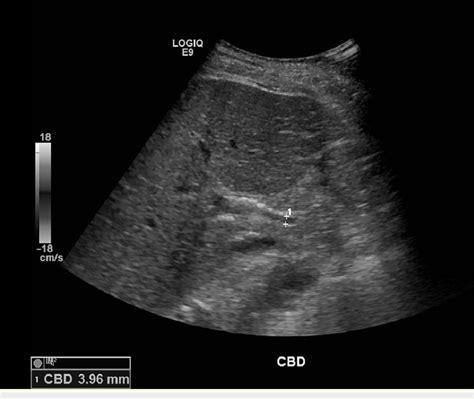

Increased echogenicity of liver causes. . ...

Increased echogenicity of liver causes. .